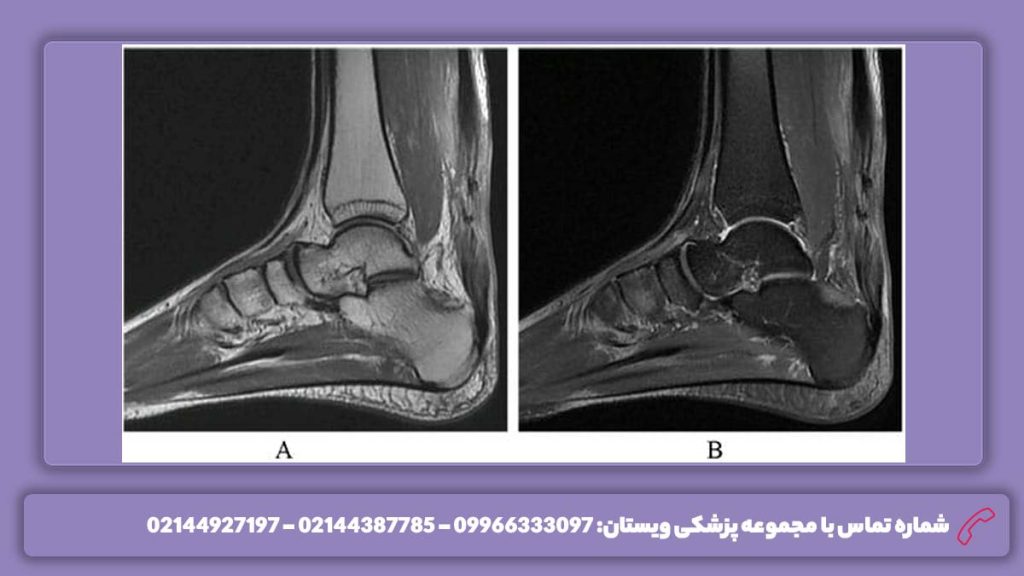

عکس آشیل پا

تصویر ساختار عضله پشت ساق پا

عکس رباط آشیل پا

عکس آشیل پا، تصویری دقیق و مهم از تاندون آشیل و ساختارهای اطراف آن است که به پزشکان کمک می‌کند تا وضعیت سلامت این تاندون حیاتی را ارزیابی کنند. این تصاویر معمولاً با استفاده از روش‌هایی مانند سونوگرافی یا MRI تهیه می‌شوند و برای تشخیص آسیب‌ها، التهاب‌ها یا پارگی‌های تاندون آشیل کاربرد دارند. عکس آشیل پا به‌خصوص در موارد درد مزمن، تورم یا محدودیت حرکتی اهمیت دارد و می‌تواند به تشخیص به موقع و برنامه‌ریزی درمان دقیق‌تر به دکتر ارتوپد کمک کند.